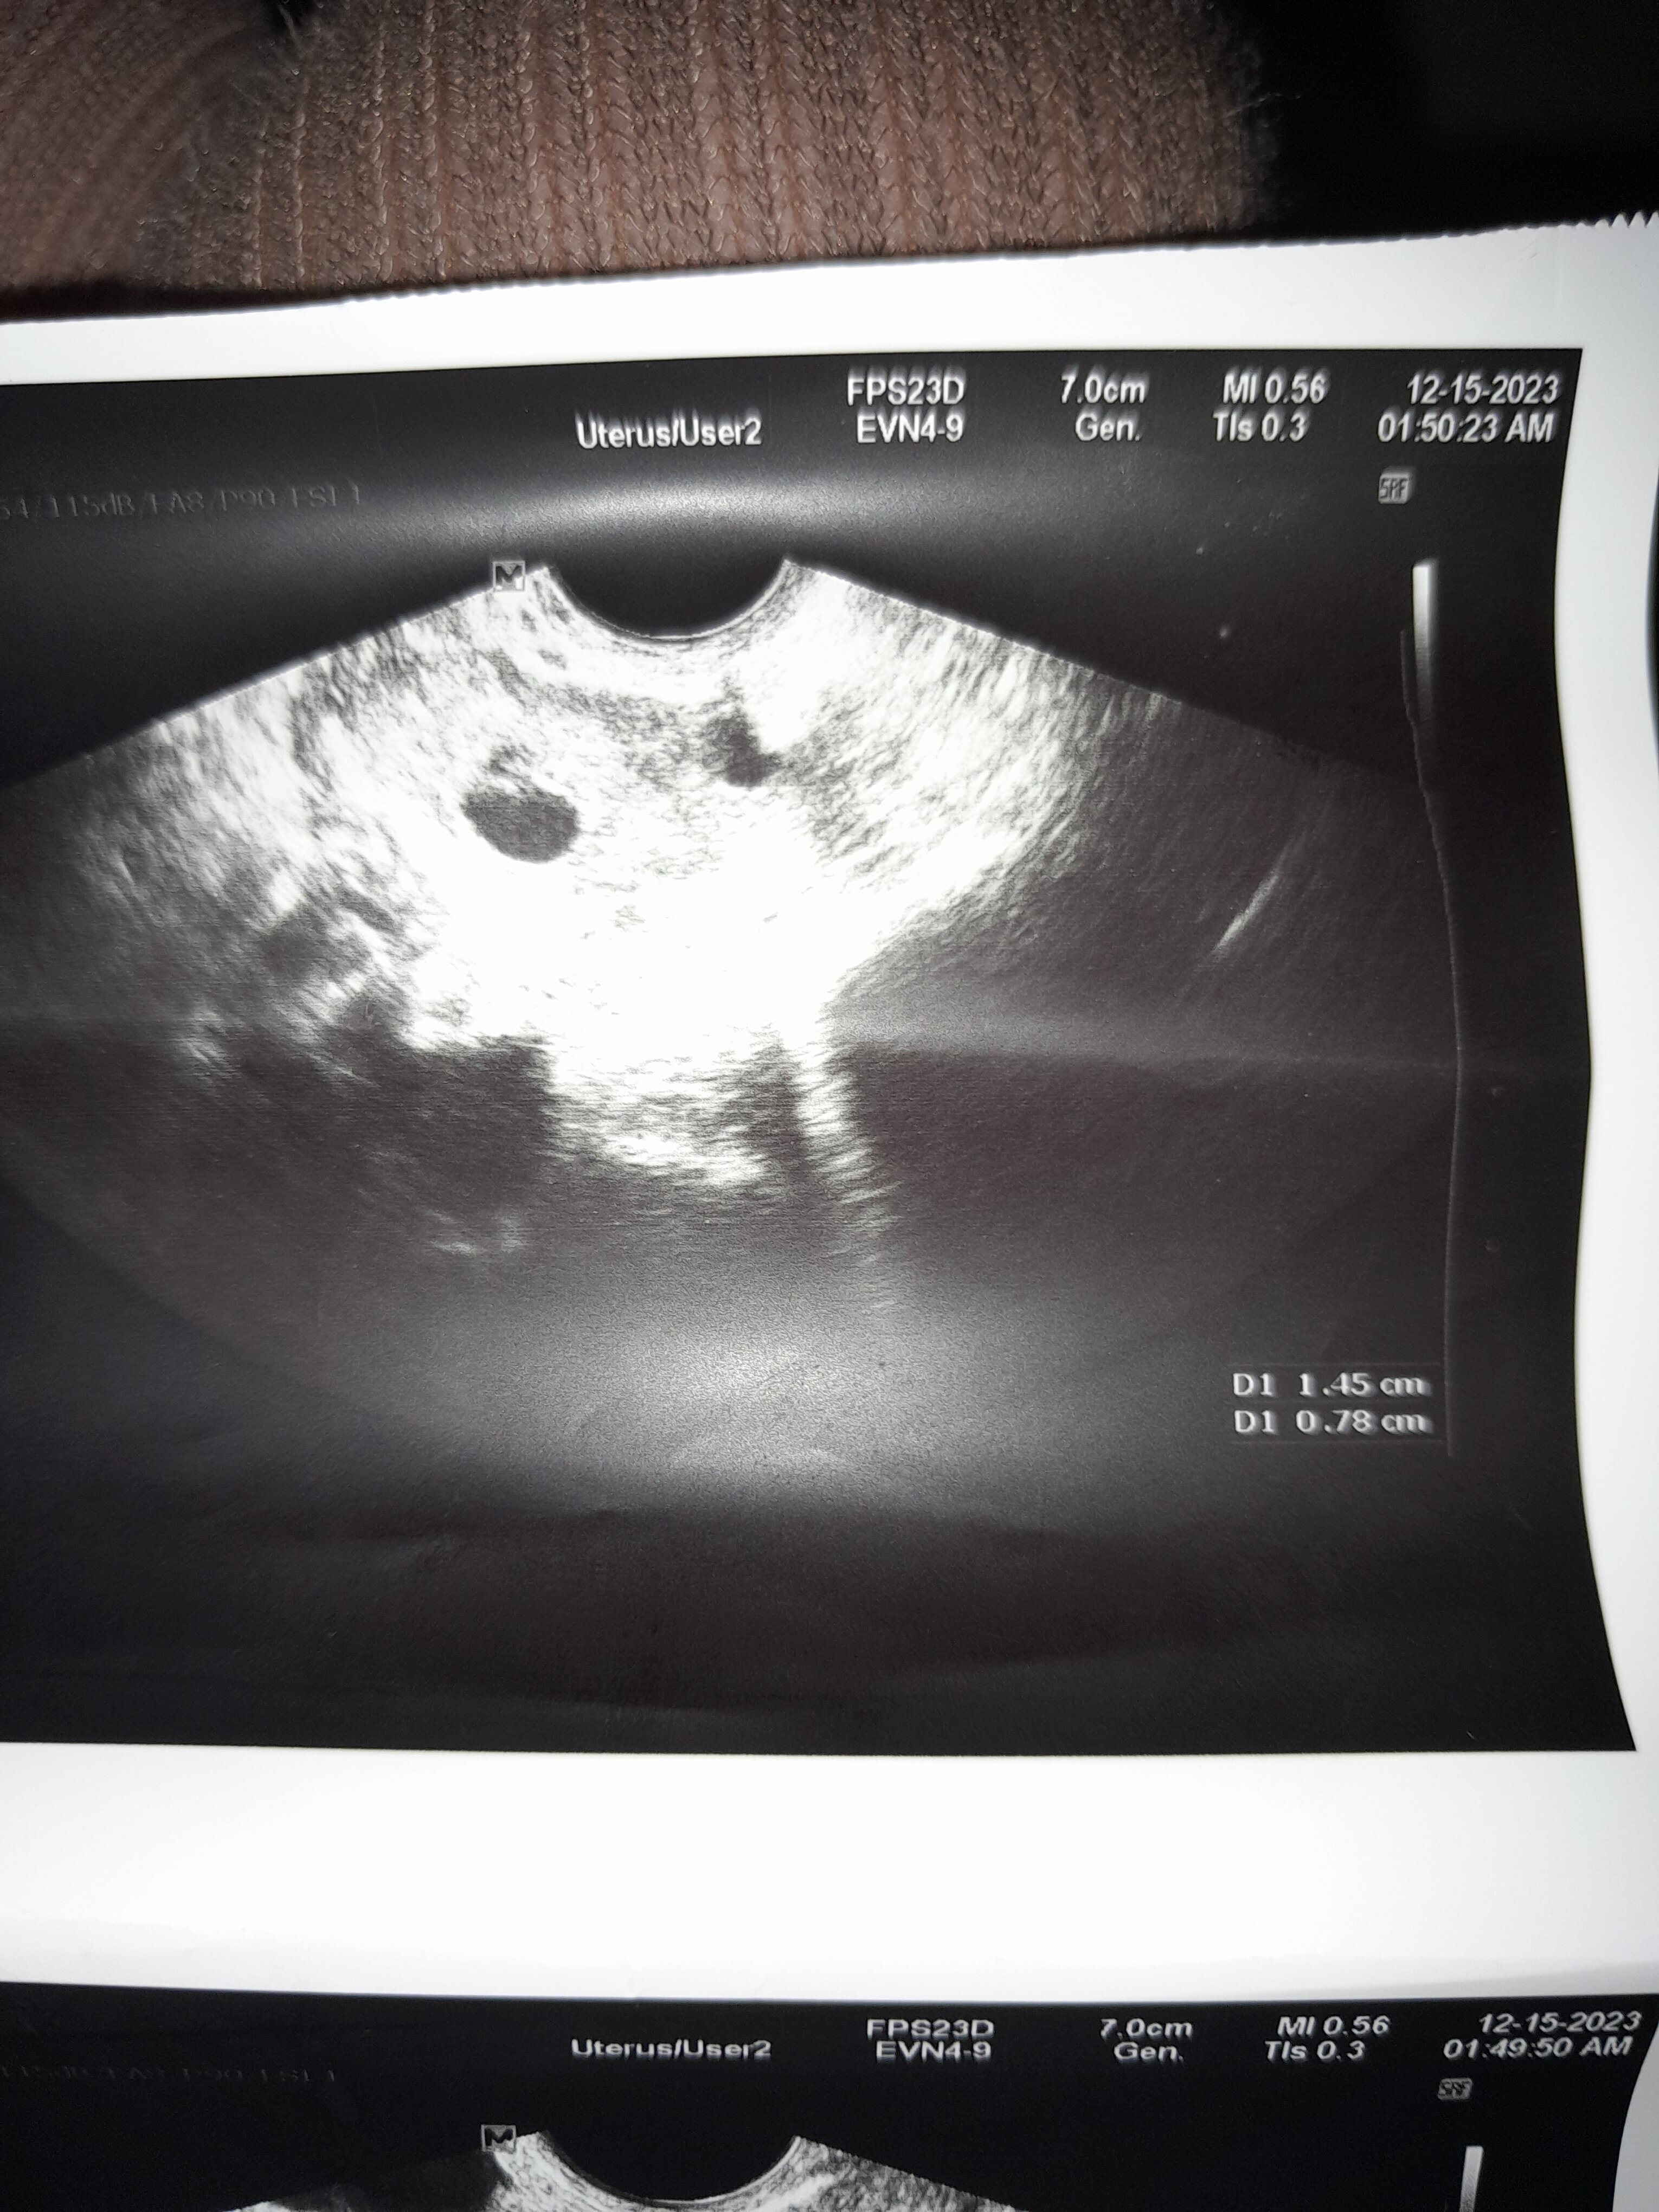

Witam mam nie nie regulalne miesisiscxki bralam progesteron besins i dzis byla. I sa 2 pechezyki ale bez cech ciazy D1 1.45 cm D1 0.78 cm i lekarz mowi ze dostalqm miesiaczke czy jest mozliwe ze beda z tego zarodki kiedy powinam zrobic hcg prosze o mam biale sluz ciagniacy i mam 37 3 tem i czy to ciaza

Lekarz powiedział, że to pęcherzyki ciążowe?